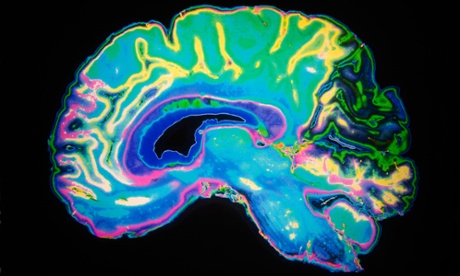

An artificially coloured MRI scan of a human brain. The latest study suggests that in Alzheimer’s, immune cells that normally protect the brain instead begin to consume a vital nutrient called arginine. Photograph: Alamy

The latest study suggests that in Alzheimer’s, immune cells that normally protect the brain instead begin to consume a vital nutrient called arginine. By blocking this process with a drug, the team from Duke University in North Carolina were able to prevent the formation of plaques and also halt memory loss in mice.